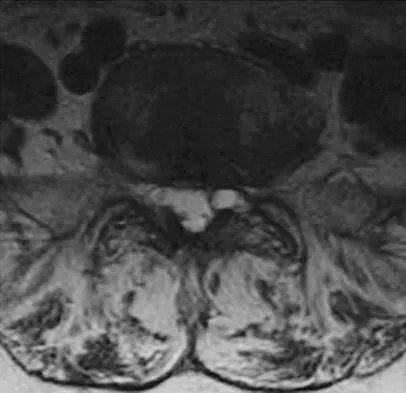

A 73-year-old woman reports a 4-month history of severe left-sided posterior buttock pain and left leg pain. The leg pain radiates into the left lateral thigh and posterior calf with cramping. Examination reveals mild difficulty with a single-leg toe raise on the left side and a diminished ankle reflex. There is also a significant straight leg raise test at 45 degrees which exacerbates symptoms. An MRI scan is shown in Figure 4. What is the most appropriate treatment at this time?

Detailed Explanation